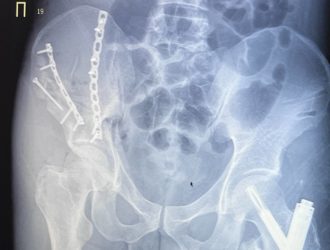

В Кузбассе врачи по кусочкам собрали сломанный таз упавшего с 4 этажа пациента

У поступившего в тяжелом состоянии 33-летнего пациента диагностировали перелом таза с центральным вывихом бедра,...